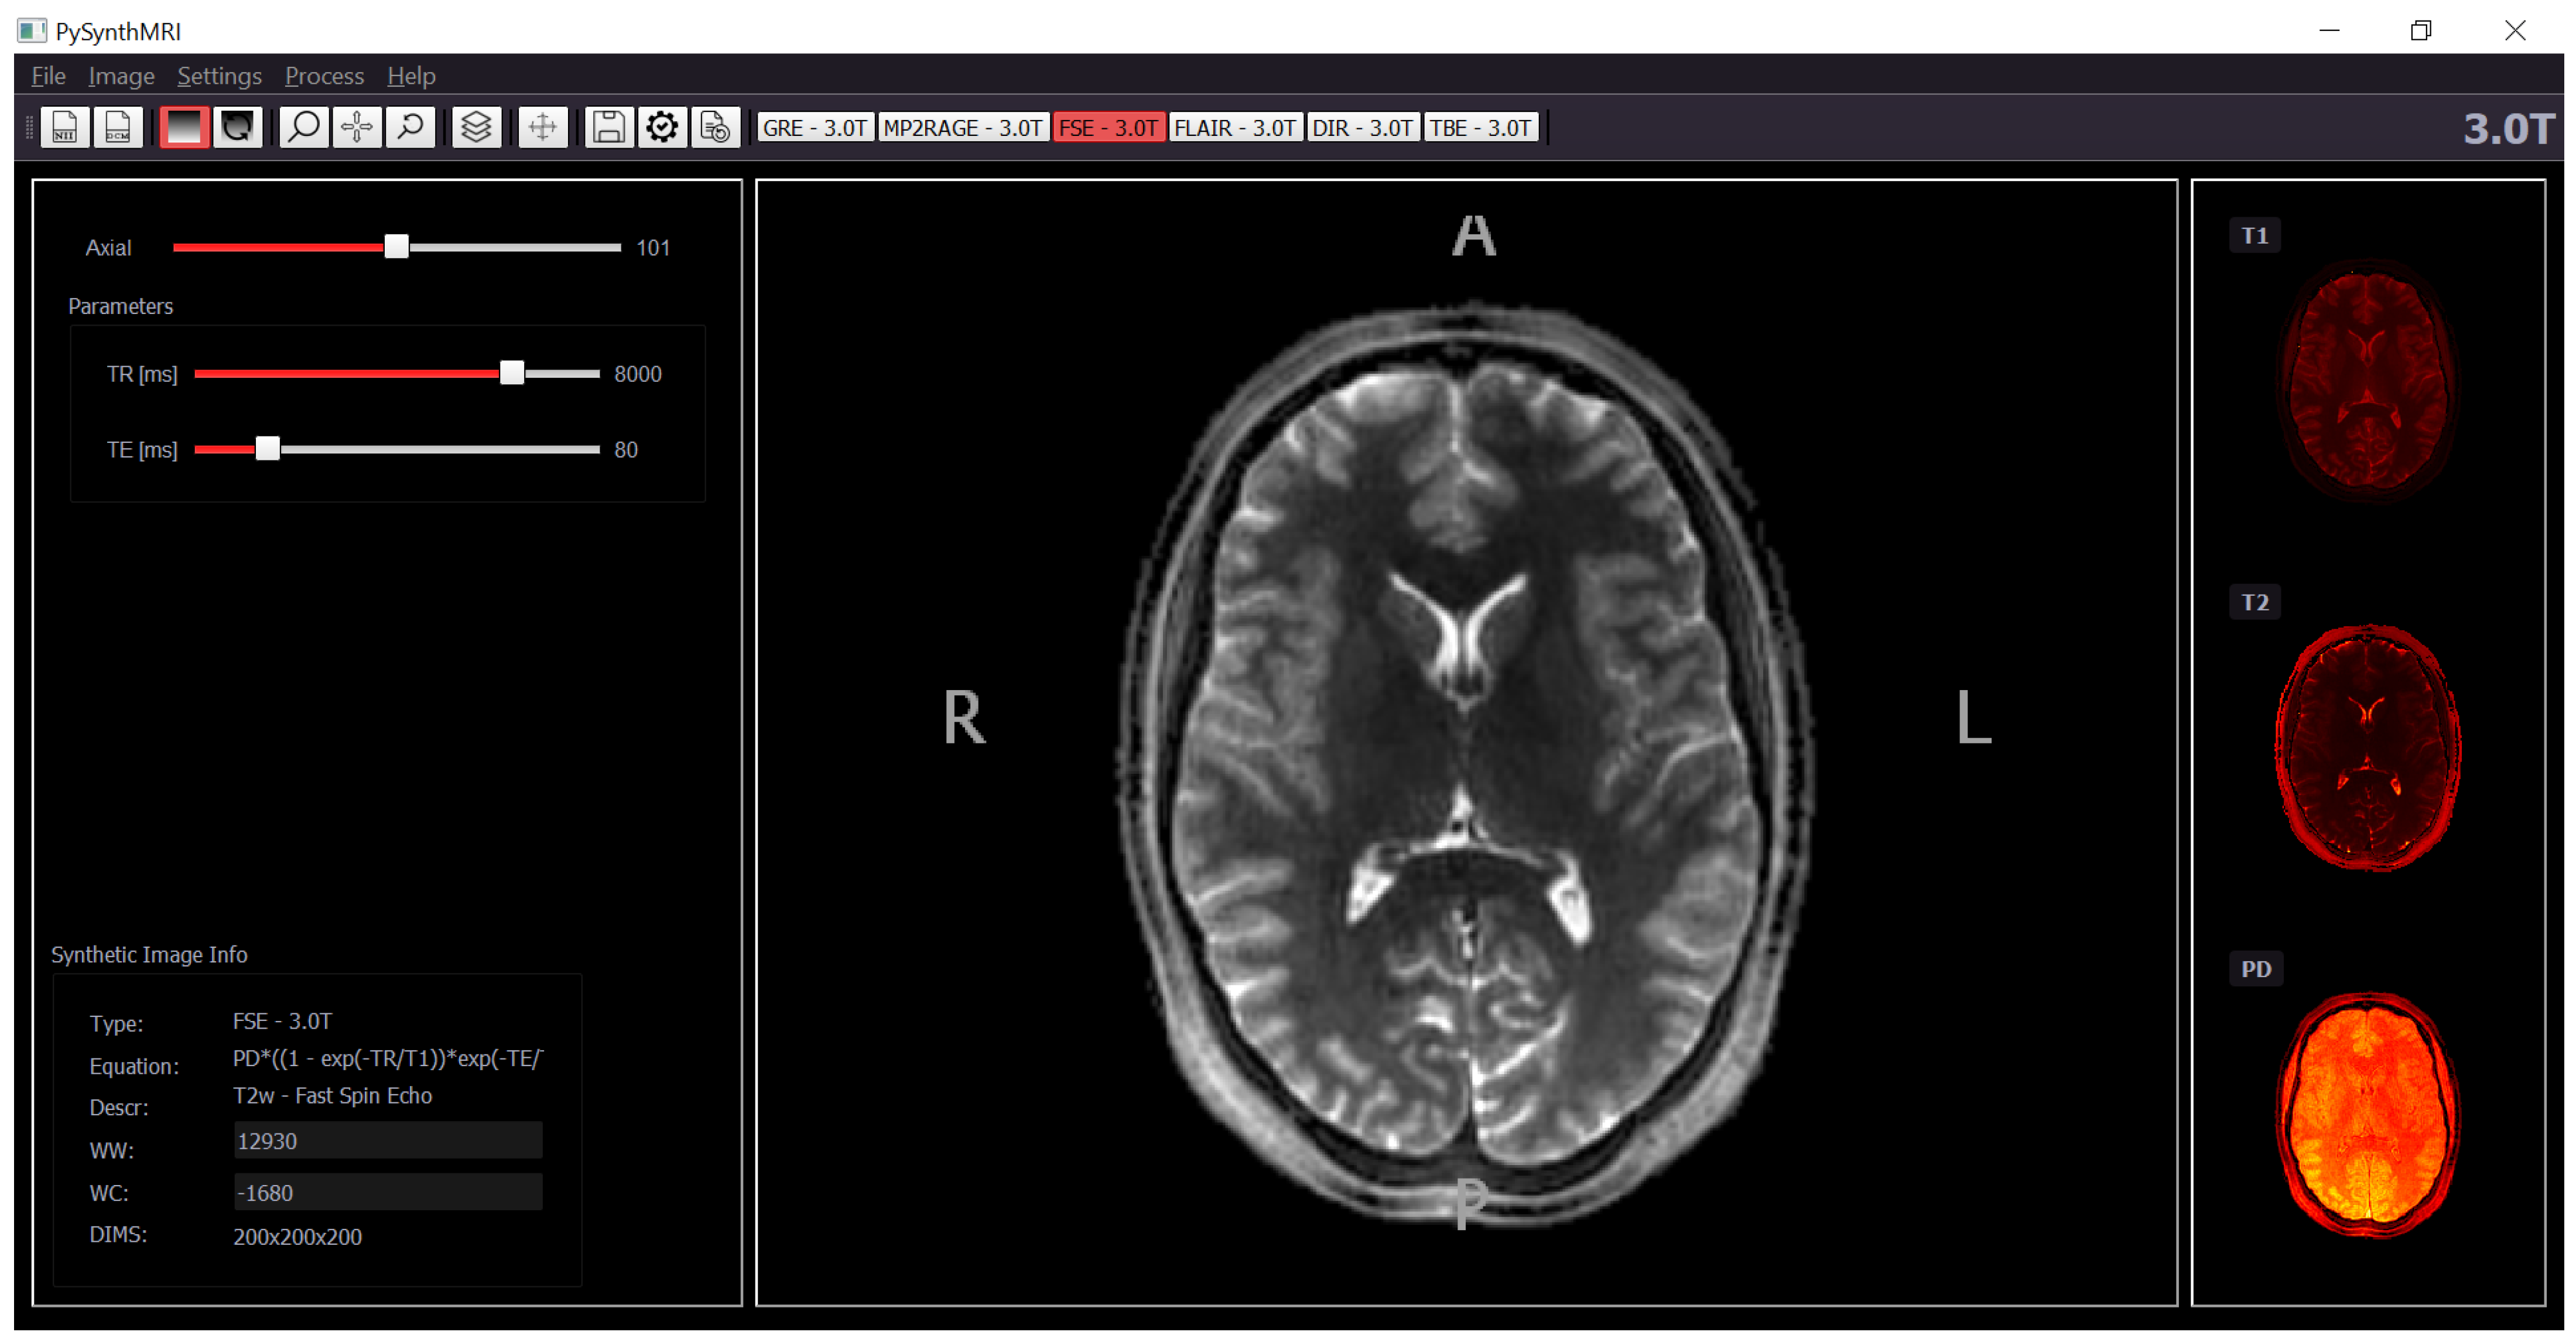

2.4. Graphical Interface Interaction